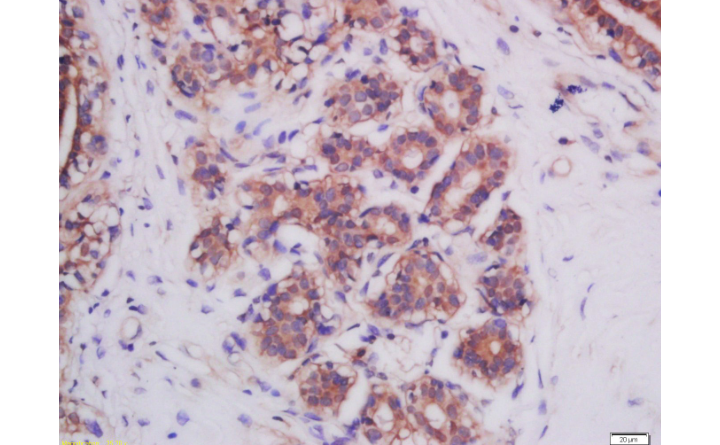

Tissue/cell: human kidney tissue;4% Paraformaldehyde-fixed and paraffin-embedded;

Antigen retrieval: citrate buffer ( 0.01M, pH 6.0 ), Boiling bathing for 15min; Blocking buffer (normal goat serum,C-0005) at 37℃ for 20 min;

Incubation: Anti-Mitofusin-2 Polyclonal Antibody, Unconjugated(bs-2988R) 1:200, overnight at 4°C; The secondary antibody was Goat Anti-Rabbit IgG, FITC conjugated(bs-0295G-FITC)used at 1:200 dilution for 40 minutes at 37°C.